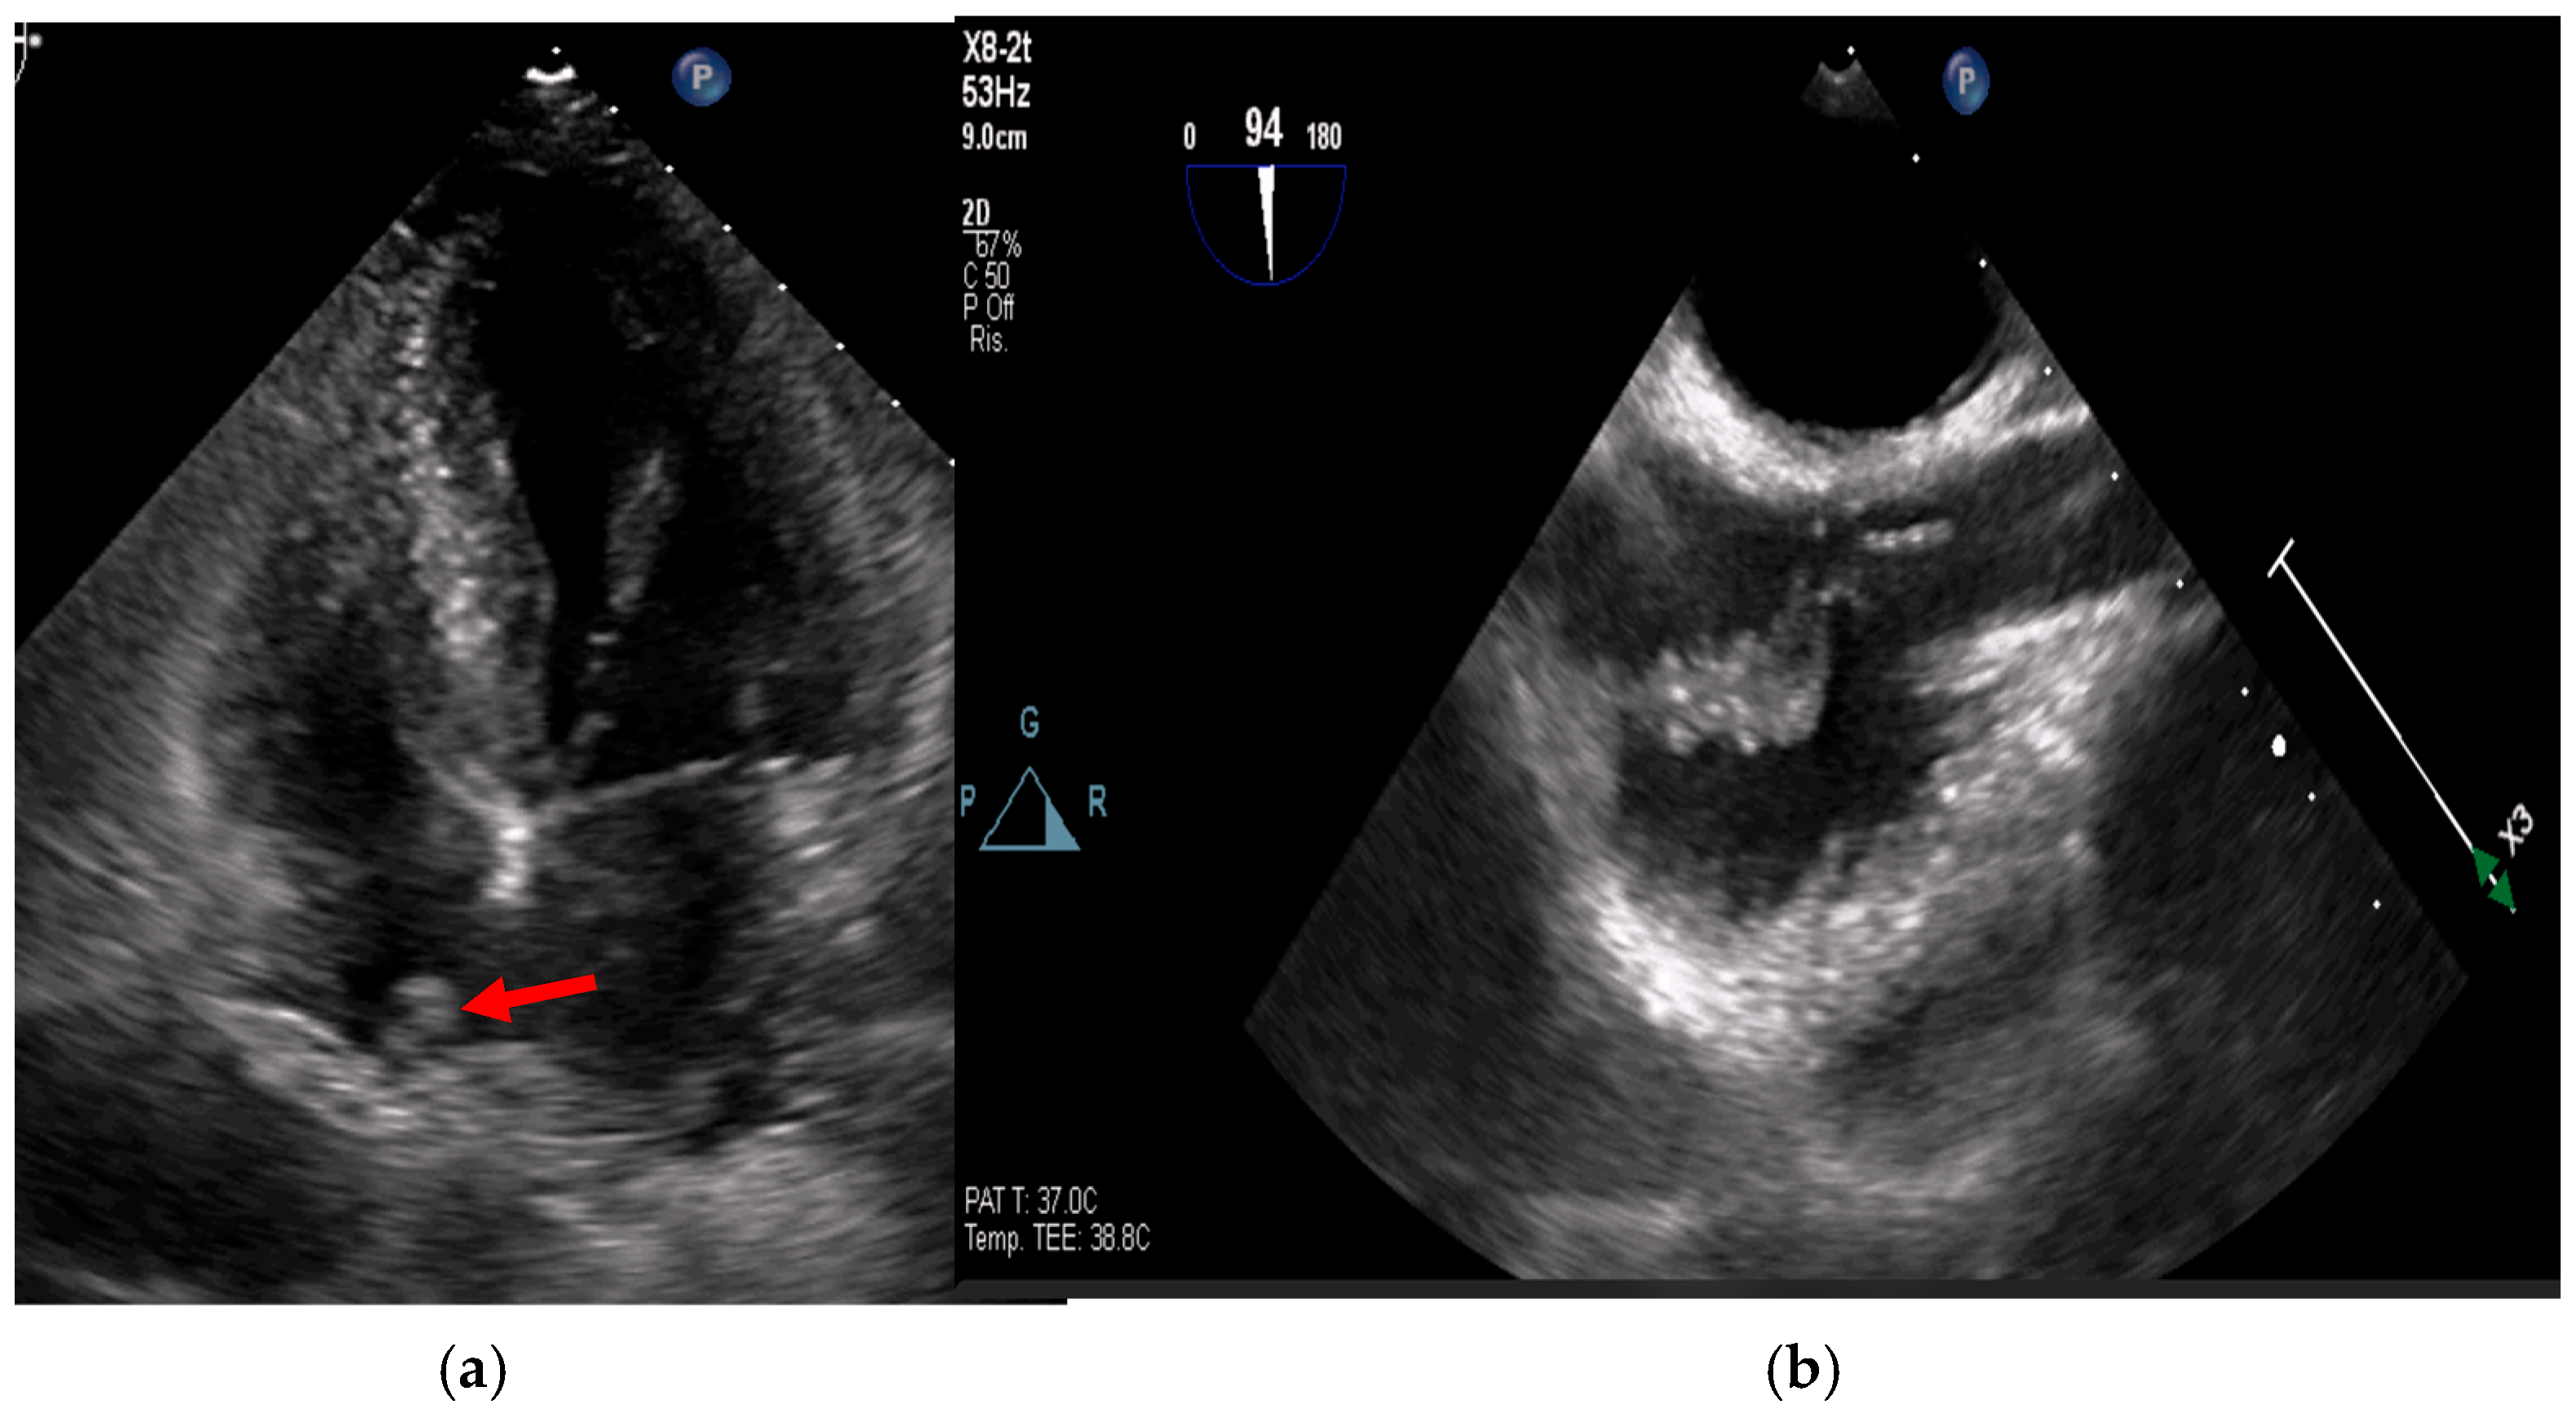

- valvular or leaflet perforation, i.e., tissue defects causing valvular regurgitation originating from the site of perforation.

- valvular aneurysm, a saccular outpouching of a valve leaflet, protruding into the atrium or ventricle.

- perivalvular or perigraft abscess, an echolucent or echodense area adjacent to the valve annulus or prosthetic ring often with irregular borders and sometimes with evidence of cavity formation.

- pseudoaneurysm, a contrast-filled outpouching with a narrow neck communicating with the cardiac lumen, often adjacent to the valve annulus. On echocardiography, it appears as a pulsatile cavity with systolic expansion and diastolic collapse.

- intracardiac fistula, visualized as an abnormal communication between cardiac chambers or vessels, is often detected by using color Doppler.

- significant new valvular regurgitation compared with previous imaging, i.e., increase in regurgitant jet size, vena contracta width…